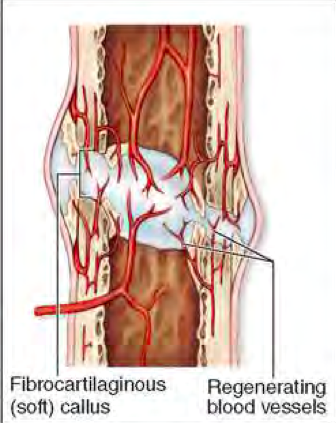

Describe the components of fracture healing present in this image?

Haematoma (left, dark purple)

Granulation tissue (next to haematoma)